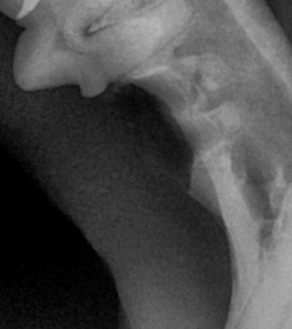

덴탈 X-ray를 통해 치아 내부 상태를 정확히 파악한 후, 아이에게 불필요한 고통 없이 최선의 결정을 내릴 수 있도록 안내합니다.

BEFORE

AFTER